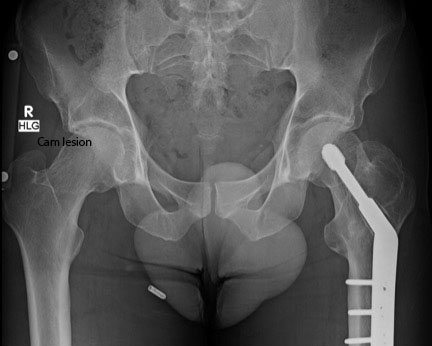

It’s an overuse injury, Pascual-Garrido said, that affects many cyclists, as well as hockey and soccer players. These athletes often have a cam impingement – a bony protrusion – that wears down the cartilage, she said.

Rogers is no stranger to pain from injuries and chronic overuse. He carries a plate and screws in his left hip and femur from a fracture sustained in a cycling crash 10 years ago and has suffered many other injures. But the right-hip discomfort eventually led him to treatment with CU Sports Medicine orthopedist Omer Mei-Dan, MD. Mei-Dan administered two rounds of cortisone shots, and later injected platelet-rich plasma in the joint to promote healing.

The procedures gave Rogers relief from the pain, and they helped him to get through the 2015 season. By the end of it, though, the effects had started to wear off. He explored surgery to repair the damage with Pascual-Garrido, who defined the extent of the injury with imaging. It showed that Rogers had a severely torn labrum, the result of the large bump on the head of the femur that prevented the joint from moving smoothly – the last thing a cyclist wants.